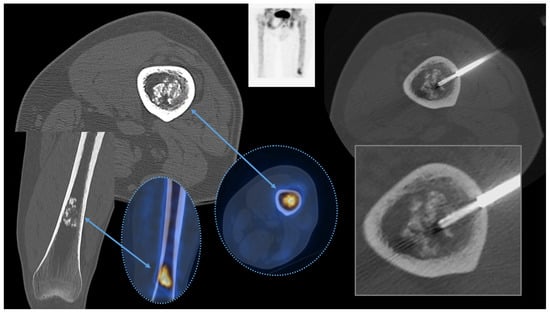

2.6. Appendicular Skeleton